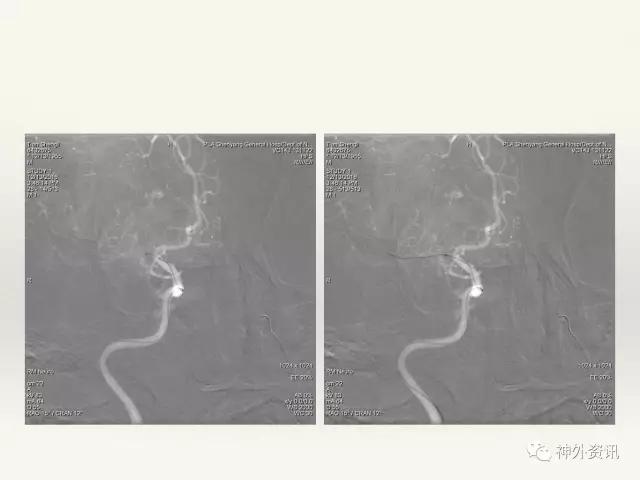

在东北地区率先开展了颈内动脉、大脑中动脉及基底动脉闭塞血管内再通、颅内动脉栓塞急性期取栓、血流导向装置治疗大型宽颈动脉瘤等,对颅内动脉瘤、动静脉畸形、颈动脉及颅内动脉狭窄、颈内动脉海绵窦瘘、硬脑膜动静脉瘘等外科治疗具有较深的造诣。完成脑血管造影8600余例,各类脑血管病介入手术共4500余例,动脉瘤、动静脉畸形、脑肿瘤、脑出血及脑外伤等外科手术1500余例。